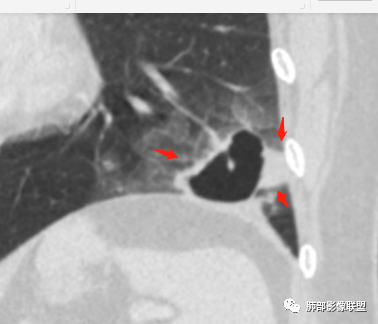

病灶分两部分

周围大片GGO

中央囊实性病变

南边:

病史没提咳血,周围出血灶似乎不太好说

部分边界偏清

囊腔有张力,外形有分叶,壁厚薄不均,有间隔,有强化

哪些病变可能?

影像特点:

1、左肺下叶外基底段不规则囊腔样病灶,囊腔内有条形影及血管穿行。

2、囊壁薄厚不均匀,稍显僵硬,有壁结节(对应边缘分叶等)、结节强化明显。

以上两条几乎将肺囊肿彻底排除在外,且高度怀疑新生物!

3、灶周环以大范围磨玻璃影,非常均匀,没有重力分布趋势,分叶状,边界隐约可变。

4、冠状位部分层面可见支气管在囊腔边缘截断。